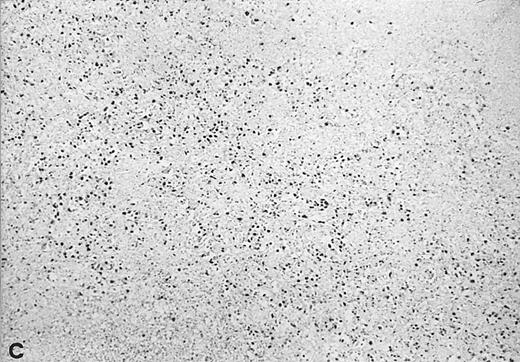

The relative amount of EBV DNA in the EBV+ samples was estimated by comparing the OD values of their amplified EBNA2 products to the OD values obtained using standard reference samples, as detailed in Materials and Methods. As shown in Table 3, most of the EBV+ lymphadenopathy samples had very low levels of EBV DNA (ie, scored either 1+ or 2+) and accordingly, none of the analyzed lymphadenopathy specimens was found to be EBV+ by Southern blot analysis. Three cases were analyzed by in situ hybridization with EBER probes; 1 (no. 20) showed viral sequences in 2% to 3% of cells (Fig 3), and 2 (nos. 21 and 23) were negative. Interestingly, in 4 of 6 coinfected lymphadenopathy cases, the amounts of type 1 and type 2 EBV DNA were equivalent, while either type 1 or 2 predominated in the 2 remaining cases (Table 3).

In situ hybridization with EBER probes. In a representative lymphadenopathy case (no. 20), rare EBER+ cells are seen, mainly in the interfollicular areas (A and B). In a representative lymphoma case (no. 46) nearly half of the cells are EBER+ (C and D). Original magnification: ×130 (A and C) and ×260 (B and D).

Twelve of the 16 EBV+ lymphoma samples scored from 3+ to 6+ for EBV DNA content (ie, 102- to 105-fold higher than that found in the majority of the lymphadenopathy samples), and most were also positive by Southern blot analysis (Table 4). Seven of 11 tested samples were also positive for viral sequences by in situ hybridization with EBER probes (Table 4). Although the high content of EBV in these tumors strongly indicated that they arose from the proliferation of EBV+ cells, 4 large cell lymphomas contained consistently low levels of EBV DNA, a finding that might reflect either a dilution effect by nonneoplastic EBV− cells in the analyzed samples, or the presence of few infiltrating reactive EBV+ B cells.